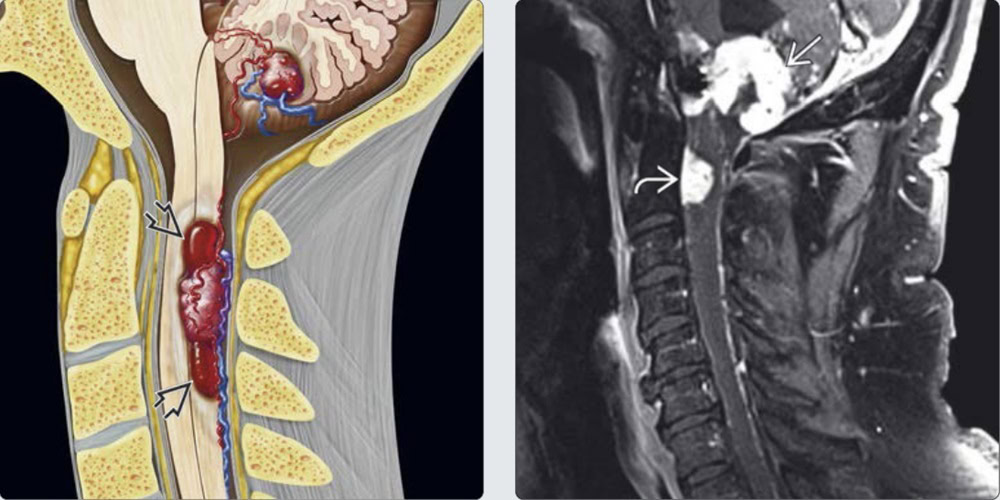

Dị dạng mạch máu thể hang (Cavernous malformation) thường cũng được gọi là u máu thể hang (Cavernoma). Chúng xuất hiện một cách ngẫu nhiên hoặc có thể có tính chất gia đình. Về mặt đại thể, các dị dạng mạch máu thể hang có đặc điểm giống quả dâu (mulberry) với các múi đỏ mọng. Chúng có kích thước từ 2mm đến một vài cm. Về vi thể CMs gồm có các mao mạch dãn, thành mỏng với một lớp nội mô lát, và lớp áo ngoài (adventitia) sợi mỏng…